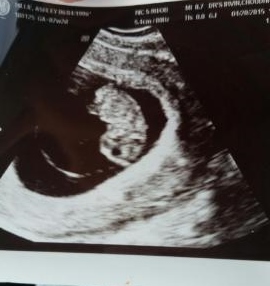

I had a transvaginal ultrasound done at 8 weeks. I've tried to use the Ramzi Method to determine the gender but honestly have no clue what I'm looking at. Please help.

Maybe girl!